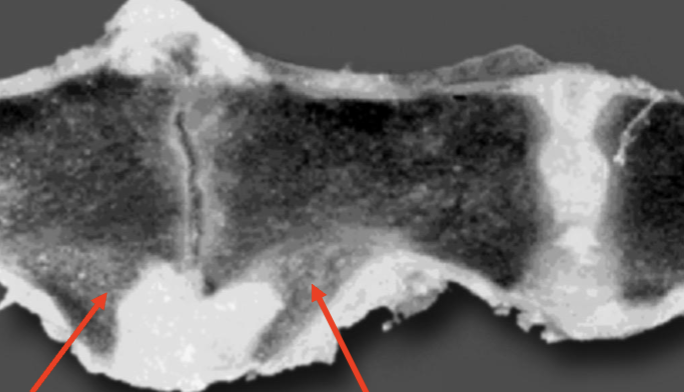

What is shown in this image?

A

spondylosis deformans